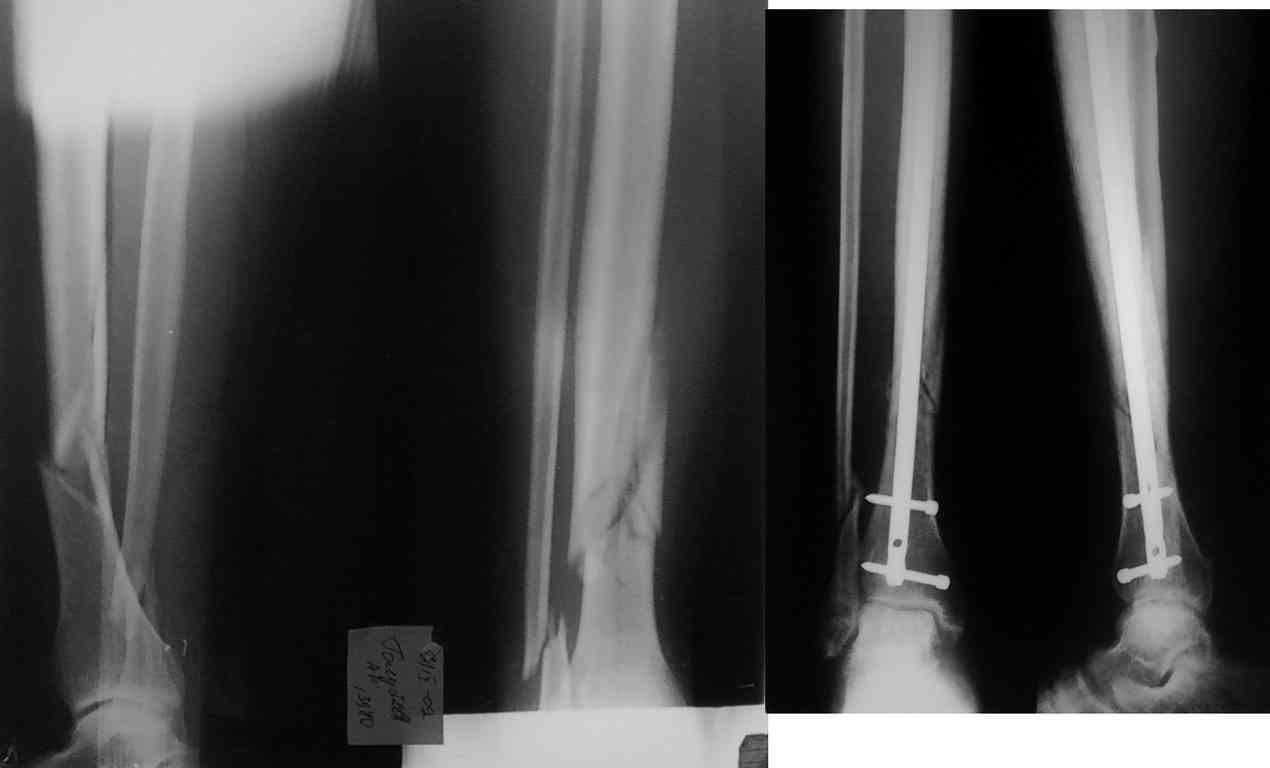

Пациент Г. 40 лет. 7 сентября 2009 госпитализирован в травматологическое отделение, через 1 час после производственной травмы с диагнозом: закрытый неосложненный оскольчатый перелом правой голени в с-н/3. 23 сентября выполнен БИОС правой б/б кости польским стержнем. Задержка в операции обусловленна высокой температурой в первые 10 дней, затем на узи - тромбоз сурального синуса справа и после консультации сосудистого хирурга и антикоагуляционной терапии выполнена операция. Выписан на 10 сутки с рекомендацией ходить с дозированной нагрузкой. Пациент результатом доволен.

А теперь сама суть проблемы. В виду того, что травма производственная пациент купил на свои деньги данную конструкцию (ему предложены были все возможные способы лечения и операции, о чем имеется информированное согласие) не дожидаясь, когда это сделает его предприятие. Но после выписки деньги за конструкцию ему не возместили и он подал в суд. Меня дважды вызывали на свидетельские показания, для разъяснения целесообразности такой операции. Но теперь работодатель привлек консультанта профессора из другой области (извините имя его не называю, а то ему передадут это сообщение). Где он в своем письменном заключении критиковал мое лечение:

1. данную операцию можно было выполнить накостным и внутрикостным бесплатным фиксатором (мое мнение, что это глупость)

2. на 16 сутки после травмы и на ДСВ - блокируемый гвоздь это лишнее, можно и простым стержнем, т.к. там уже формируется достаточно крепкая мозоль (мое мнение - бред)

3. тромбоз сурального синуса не противопоказание ждать 16 дней (мое мнение - первые 10 дней температура, затем узи, потом сосудистый хирург - уже 12дней получается, а потом выходные и уже операция, итого 16)